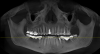

AlexandreD Опубликовано 9 августа, 2012 Автор Поделиться Опубликовано 9 августа, 2012 Добавил снимок. Ссылка на комментарий

Force Опубликовано 9 августа, 2012 Поделиться Опубликовано 9 августа, 2012 восьмерки с таким наклоном при перемещении просто лягут... Удалять и не думать.Вариант кроме имплантации - съемный протез... Ссылка на комментарий

IvanK Опубликовано 10 августа, 2012 Поделиться Опубликовано 10 августа, 2012 восьмерки с таким наклоном при перемещении просто лягут... Удалять и не думать.Вариант кроме имплантации - съемный протез...+1 + санация, наверху тоже есть проблемы Ссылка на комментарий